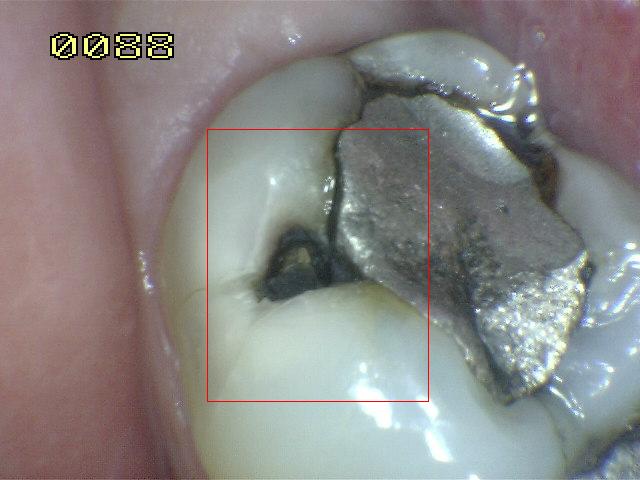

¿Determine los códigos pertinentes a cada imagen?

Click en el hipervínculo: Para comparar el resultado de su diagnóstico